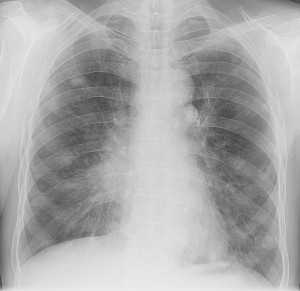

Метастазы в легких — фото рентгенограммы. Округлые тени — метастазы рака пищевода. Хорошо виден большой узел округлой формы вблизи переднего отрезка 2-го ребра. На снимке справа - циркулярное сужение пищевода за счет опухолевого утолщения его слизистой оболочки.

Как выглядят метастазы в легких на рентгене? Слева — узловые образования у пациента с раком яичка. Справа - метастазы рака яичников гематогенного характера с выраженным опухолевым лимфангиитом (обратите внимание на деформированный сетчатый, линейный характер легочного рисунка).